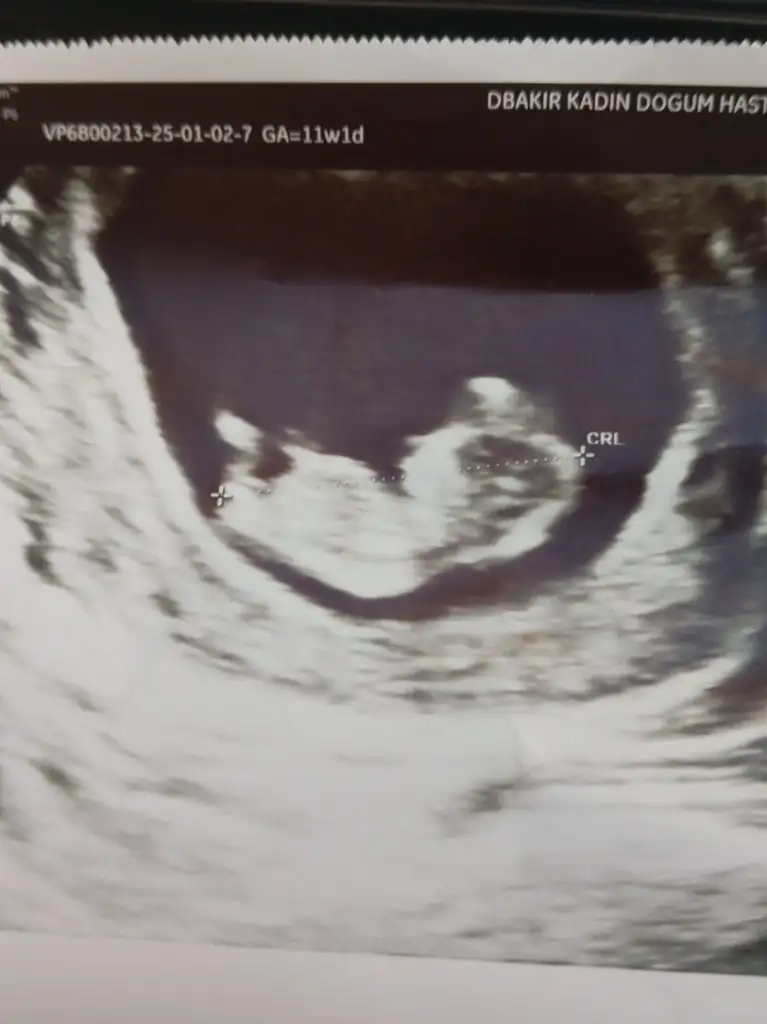

Arkadaşlar merhaba daha önce burada ultrason fotoğrafına bakıp cinsiyet tahmin edenleri görmüştüm benim içinde bi heyecan olur:) var mıdır tahmininiz normalde 12+4 üm ama ultrasonda 13 haftalık görünüyor.

Benimde 13+1 de karından ultrason ile bakıldı tahmin de bulunabilir misiniz 🙏